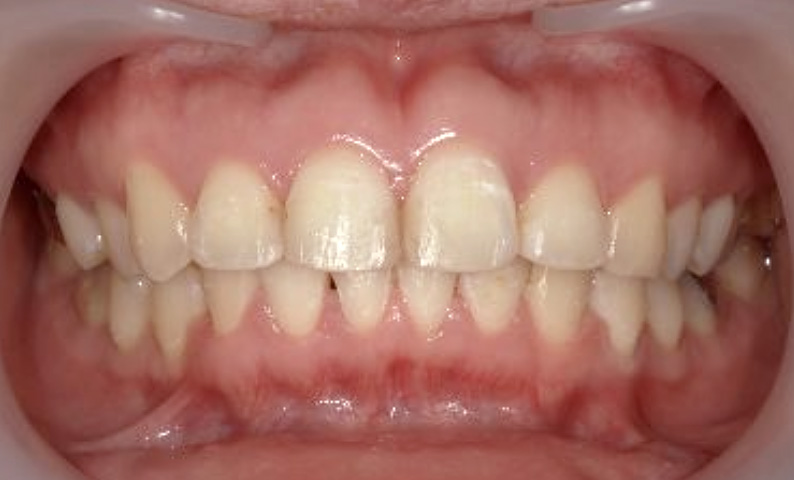

症例_024 上下顎の部分矯正

治療期間:13ヶ月金額:51万円+税女性前歯のガタガタ八重歯

| Before | After |

|---|---|

|